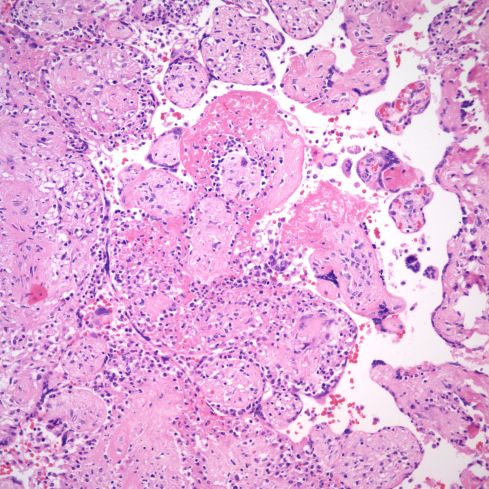

These lesions of larger stem villi may show endovascular lymphocytes and thrombus (Fig 24-26).

Fig 24) The stem villus shows eccentric inflammation and destruction of a portion of the vessel wall, and fibrin deposition. In the upper left corner the connecting and adjacent villi show VUE and the syncytial surface of the stem villus shows necrosis and lymphocytic inflammation. (H&E, 10x)

Fig 25)This stem vessel in an area of villitis shows lumenal thrombus and inflammation of the vessel wall. (H&E, 20x)

Fig 26 There is a large, organizing thrombus in a stem villous vessel with VUE in the adjacent and connected villi. (H&E, 20x)